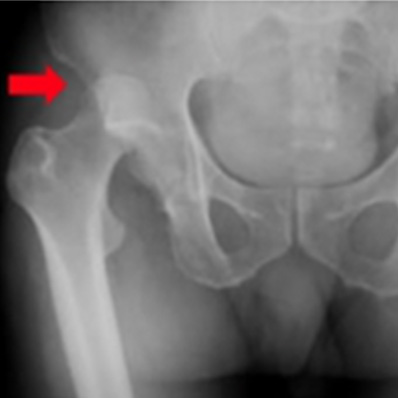

大腿骨転子部骨折

人工股関節術後脱臼